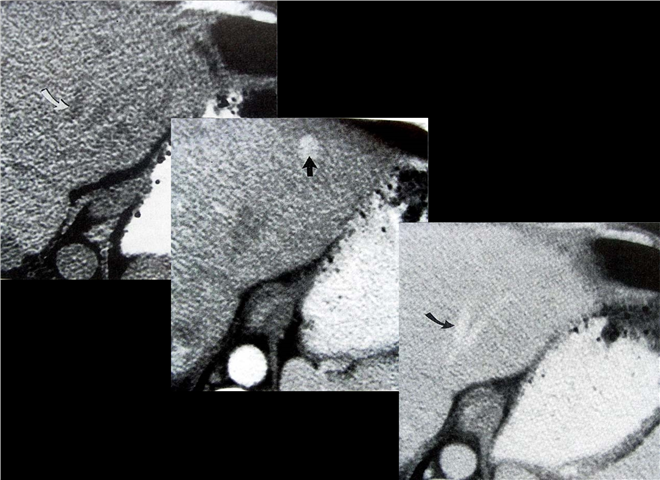

13_CT增强扫描